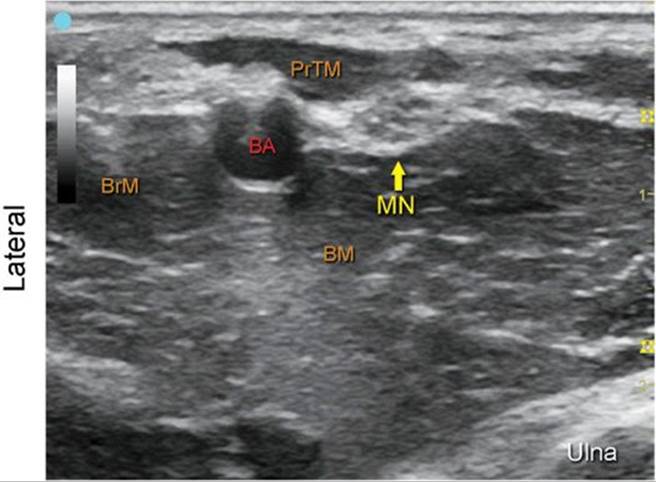

Median Nerve at the Elbow

FIGURE 7.24.1A Ultrasound transducer position to image the median nerve at the elbow.

FIGURE 7.24.1B Ultrasound image of the median nerve at the elbow.

FIGURE 7.24.1C Labeled ultrasound image of the median nerve at the elbow.

FIGURE 7.24.1D Labeled cross-sectional anatomy of the median nerve at the elbow.

Abbreviations: MN, Median Nerve; BM, Brachialis Muscle; BA, Brachial Artery; PrTM, Pronator Teres Muscle; BrM, Brachioradialis Muscle.